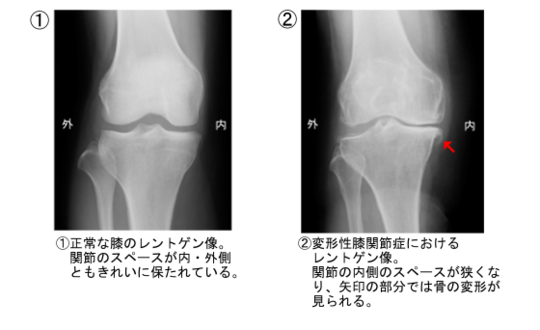

変形性膝関節症 その1

膝の関節にある軟骨が、変性したり、磨耗したり、時には異常な増殖性の変化をする状態を変形性膝関節症、あるいは変形性膝関節炎と言います。

大腿骨と脛骨の中間にある関節軟骨が磨り減り、変形して骨同士が直接接触するようになって、痛みや腫れ、水の貯留などを起こします。

関節の変形

変形性関節炎は、どちらかと言うと「O脚」の人に多く出現する病気です。膝関節の内側の関節軟骨がすり減り、ますます「O脚」状態が進行します。